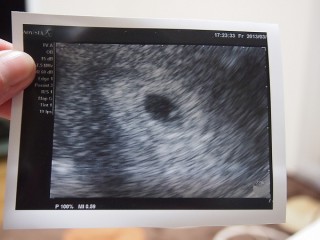

出血があり心配でしたが、心拍が確認できました♡ 大きさも通常でした!!!

まだまだちっちゃくて、ここから子供になるって、すごく神秘的